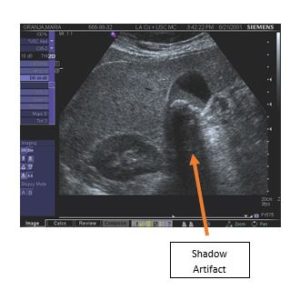

Finally, one point about general image quality complaints as they can occur because of system failures (dead transmitters), transducer failures (e.g., dead elements), or are naturally occurring phenomenon such as shown and described below. Image artifacts may occur within the transducer field of view displayed on the monitor and do not represent actual anatomical structures (see example diagram and clinical image below). They are often reported as system or transducer failures. However, image artifacts may also be caused by system limitations or operation, as well as the laws of physics. Artifact types include reverberation, attenuation, transducer, refraction, spectral, and color. They are often caused by too much power, too much power at a certain depth, muscle movement during imaging, acoustic shadowing such as the area behind a gall stone, large boundary mismatches, and noise interference from outside electromagnetic sources.